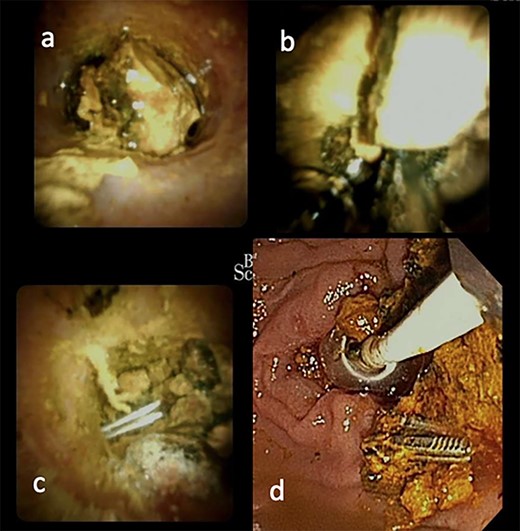

She was then referred to a larger tertiary center for spyglass cholangioscopy that enabled the surgeon to directly visualize the pathology within the bile duct. They found two surgical clips with a surrounding 30-mm stone impacted in the distal CBD. Electrohydraulic lithotripsy was used to divide the stone into smaller fragments, which were retrieved via balloon/basket extraction (Fig. 2). She was then admitted for 5 days and discharged once her liver function tests (LFTs) had stabilized.

ERCP with spyglass cholangioscopy. (a) Bile duct stone obstructing CBD. (b) EHL fragmentation of stone. (c) Two Surgical clips freed from stone material. (d) Biliary tree swept with balloon and basket.